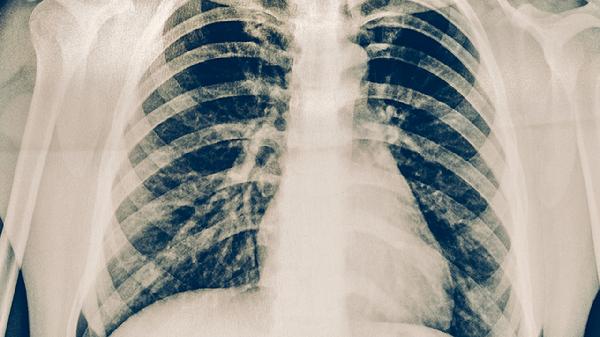

肺炎是否嚴(yán)重需結(jié)合病情判斷,多數(shù)患者經(jīng)規(guī)范治療可痊愈,但重癥肺炎可能危及生命。肺炎主要由細菌、病毒、支原體等病原體感染引起,常見癥狀包括發(fā)熱、咳嗽、胸痛等。

重癥肺炎可能出現(xiàn)呼吸衰竭、膿毒休克等并發(fā)癥,多見于老年人、嬰幼兒或免疫功能低下者。這類患者需要重癥監(jiān)護,可能需機械通氣或血管活性藥物維持生命體征。合并基礎(chǔ)疾病如慢性阻塞性肺疾病、糖尿病者,病情進展風(fēng)險更高。若出現(xiàn)持續(xù)高熱、意識模糊、血氧飽和度低于90%等情況,提示病情危重。

肺炎患者應(yīng)保持充足休息,每日飲水1500-2000毫升稀釋痰液。飲食選擇高蛋白、高維生素的流質(zhì)或半流質(zhì)食物,如蒸蛋羹、瘦肉粥等?;謴?fù)期避免劇烈運動,注意保暖防寒。吸煙者需嚴(yán)格戒煙,定期開窗通風(fēng)保持空氣流通。若咳嗽超過兩周未緩解或反復(fù)發(fā)熱,應(yīng)及時復(fù)查胸部影像學(xué)。